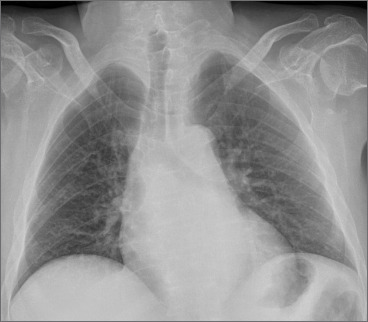

Bethlem myopathy (BM) was first described in 1976 by Bethlem and van Wijngaarden in patients who presented a myopathy characterized by slowly progressive muscle weakness and typical flexion contractures of the long finger flexors, wrists, elbows, pectoralis muscles and ankles. Patients with Bethlem myopathy usually become symptomatic during the first or second decade of life. The condition is in most cases slowly progressive and more than two thirds of patients over 50 years of age may require aids for ambulation. Inheritance is usually autosomal dominant. However, patients with autosomal recessive (AR) BM have been recently reported in Literature. Cardiac involvement is usually absent. Respiratory muscle involvement necessitating nocturnal respiratory support is rarely reported in association with severe weakness later in life.

We describe a further case of ARBM in a 52-year-old man who presented a slowly progressive myopathy but developed a severe progressive respiratory involvement requiring ventilatory support.